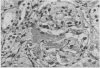

Acute renal failure developed in a 55-year-old man 6 days after he had received a cadaver renal allograft. This was associated with thrombocytopenia. Extensive intraglomerular fibrin deposition was seen in a renal biopsy specimen. He was treated with corticosteroids, azathioprine, cyclophosphamide and hemodialysis with regional heparinization but not with systemic anticoagulation. This was followed by complete recovery of both renal function and histologic damage despite the fact that he did not receive anticoagulant therapy. This suggests that treatment with anticoagulants may not be necessary for all patients with intraglomerular deposits of fibrin.